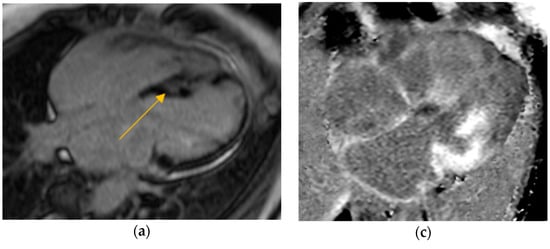

Our study found significantly greater IVSd and LVPWd in amyloidosis compared to sarcoidosis, consistent with prior reports on echocardiographic findings in amyloidosis namely, pronounced LV wall thickening and diastolic dysfunction (Figure 1 and Figure 2). Ref [24], Conversely, TTE offers limited sensitivity in sarcoidosis, functioning mainly to prompt further diagnostic imaging when regional wall thinning or basal septal changes are detected [25]. Our CMR findings revealed focal or patchy LGE in sarcoidosis, as well as mismatch uptake patterns on PET, which parallels the existing literature that utilizes CMR for structural analysis and FDG PET for monitoring active inflammation [26,27]. Our findings in the CA cohort corroborate that PYP scintigraphy (with a negative monoclonal protein screen) remains highly specific for transthyretin cardiac amyloidosis [28]. Additionally, all 19 of our CA patients undergoing CMR exhibited a diffuse pattern of LGE, highlighting the global amyloid infiltration of myocardium in contrast to the patchy granulomatous infiltration in CS. More specific measures on CMR such as Native T1 mapping and ECV measurements can indicate the extent of amyloid infiltration [29]. Unfortunately, only 19 of the 125 amyloidosis patients underwent CMR in our study, which limited the robustness of sub-analyses in this domain (Figure 3 and Figure 4).

Figure 1.

Parasternal long-axis transthoracic echocardiography (TTE) comparison. (a) Cardiac amyloidosis showing diffuse concentric left ventricular wall thickening and sparkling myocardial texture, with a small left ventricular cavity and biatrial enlargement. (b) Cardiac sarcoidosis showing normal to mildly thickened walls, with possible basal septal thinning or regional motion abnormalities, and preserved left ventricular cavity size.